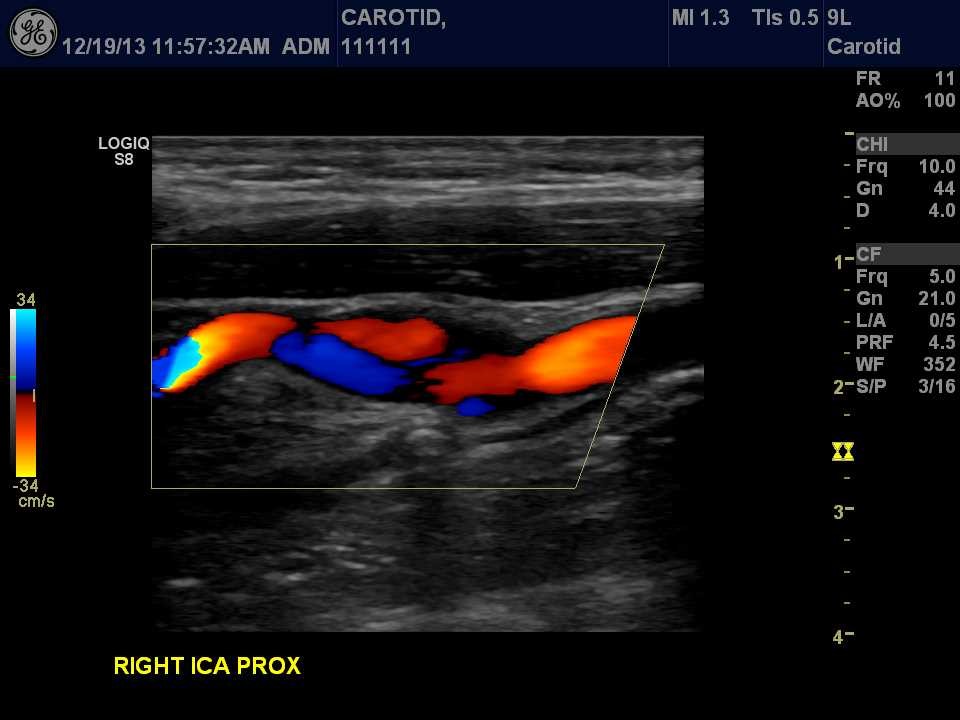

Extracranial Carotid Ultrasound Examination

When the sonographer examines the arteries going up the neck and into the brain. This includes the innominate or brachiocephalic, subclavian, vertebral, common carotid, internal carotid and external carotid arteries.

Carotid Artery Ultrasound Image